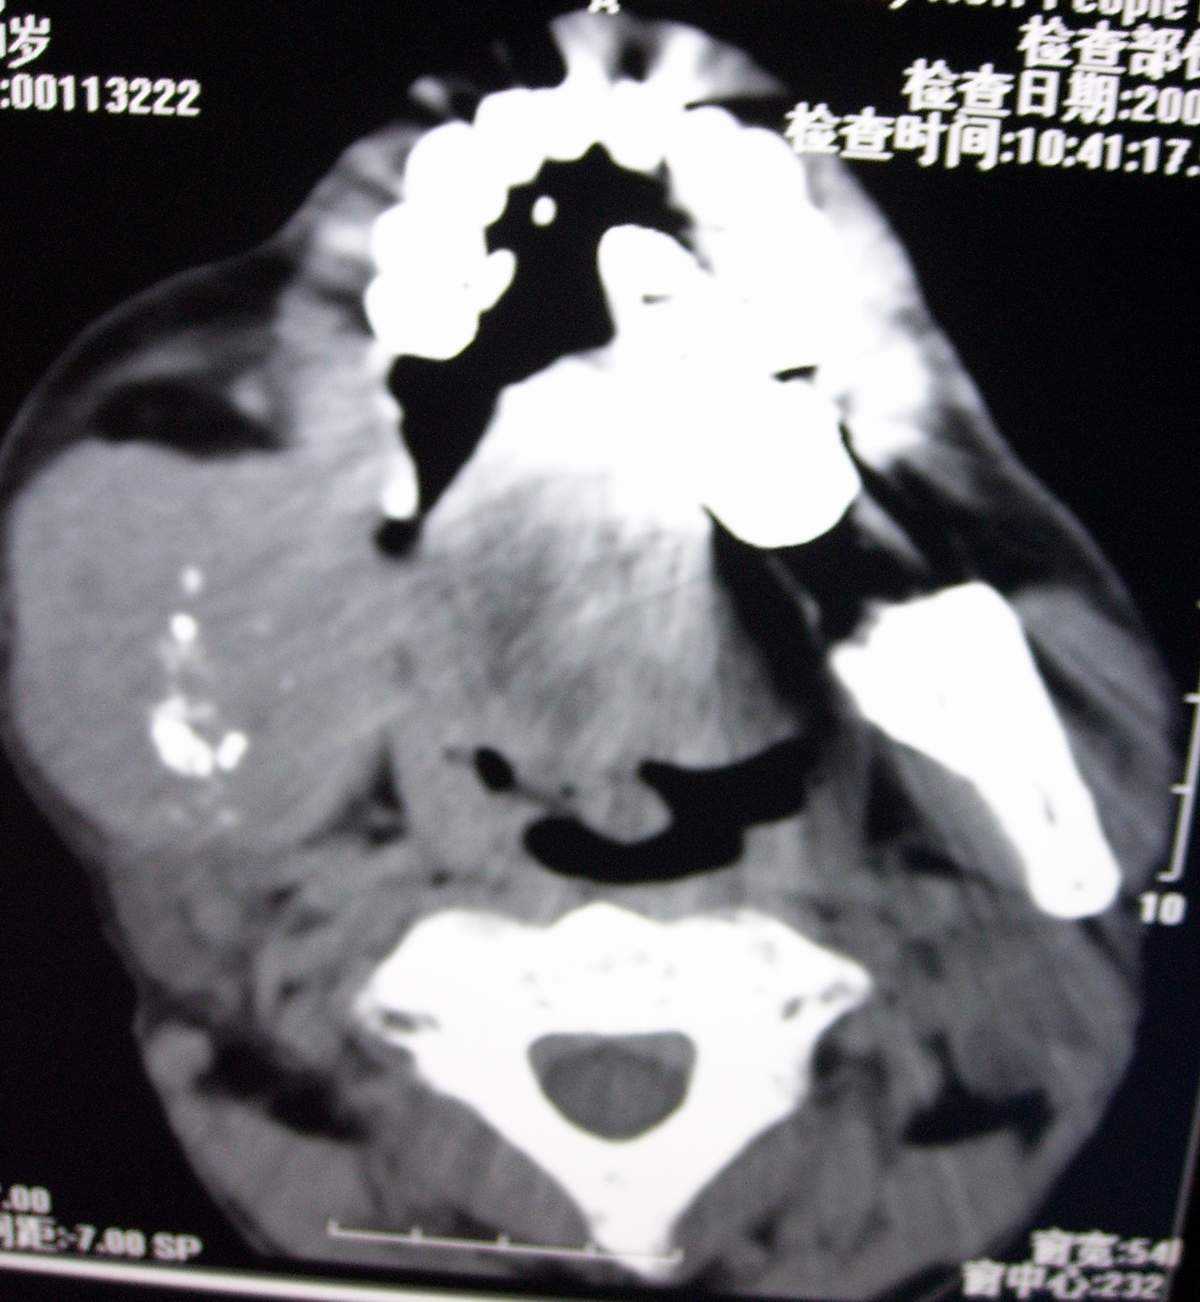

男,54岁,右下颌肿痛1月余。

右下颌骨溶骨性破坏,并见软组织形成。应考虑恶性肿瘤或转移瘤。

右侧下颌骨水平部及升支呈溶骨性破坏,无明显膨胀,周围见软组织肿块。

考虑:右侧下颌骨恶性肿瘤或转移瘤。

右下颌骨溶骨性破坏,代之以团块状软组织影,内有斑片状瘤骨,边缘骨质有少量骨膜反应,考虑:右下颌骨骨肉瘤。期待病理。